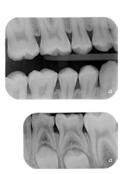

01. Hình ảnh độ phân giải cao cho chất lượng chẩn

đoán cực chất

VistaScan Nano Easy mang lại hình ảnh sắc nét hơn đáng kể so với phim X-quang.

Hiển thị rõ hơn, chính xác hơn các vết thương ở mức sâu răng D1 và dụng cụ nội nha lên đến ISO 06.